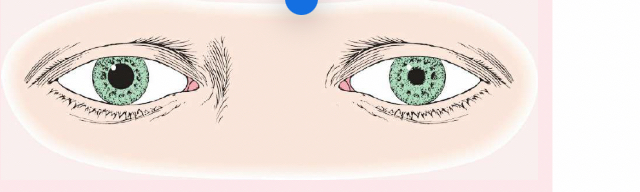

Pseudostrabismus

Normal in young children, the pupils will appear at the inner canthus (due to the epicanthic fold).

Strabismus (or Tropia)

A constant malalignment of the eye axis, is defined according to the direction toward which the eye drifts and may cause amblyopia.

Esotropia

(eye turns inward).

Exotropia

(eye turns outward).

Phoria (Mild Weakness)

Noticeable only with the cover test, is less likely to cause amblyopia than strabismus.

Esophoria

is an inward drift and

exophoria

an outward drift of the eye.